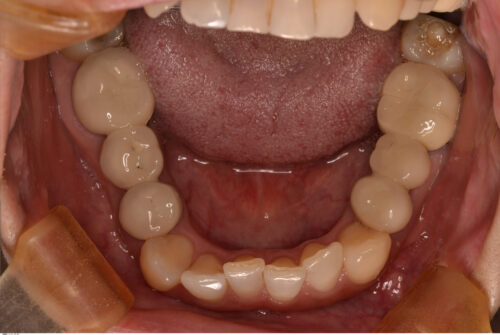

矯正治療を開始します。

上顎は骨が硬くないので容易に移動しますが

下顎は骨が硬いのでなかなか動いてくれません。

本来であれば欠損部分も矯正によってスペースを無くせばブリッジを入れる必要がなくなるのですが、下顎は骨が硬いため移動に時間がかかります。治療期間を短くすることで患者さんの負担も減るので、成人矯正の場合は補綴処置を組み合わせながら治療計画を立てることも重要だと思います。